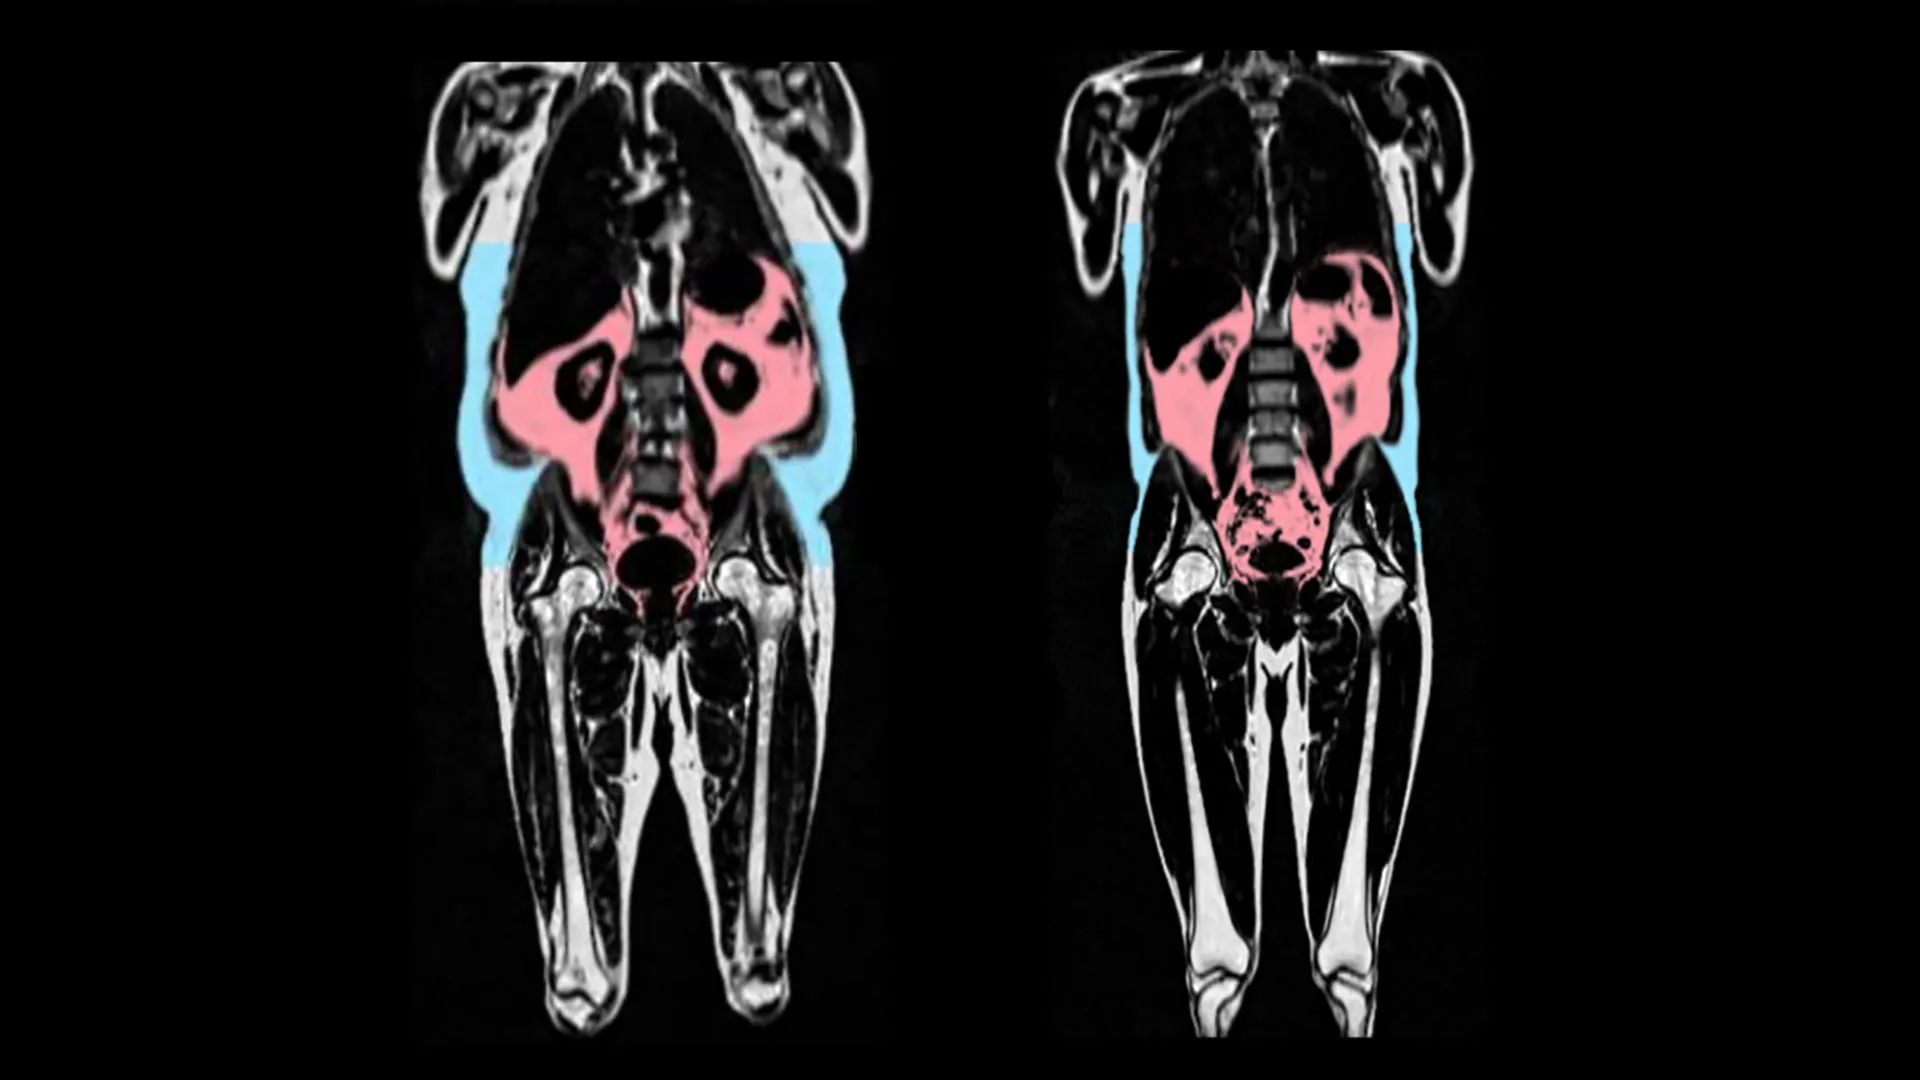

Two MRI scans, showing the person on left with more visceral fat (in red) and subcutaeous fat (in blue). Credit: AMRA Medical

The researchers found that faster heart aging was linked to having more visceral adipose tissue. Visceral adipose tissue is fat found deep inside the abdomen around organs such as the stomach, intestines, and liver. This type of fat cannot be seen from the outside, and some people can have large amounts of visceral fat despite having a healthy weight.